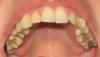

Tatil Опубликовано 11 июля, 2008 Поделиться Опубликовано 11 июля, 2008 (изменено) Добрый день! Подскажите, пожалуйста, наиболее рациональный, на ваш взгляд, план лечения.Мне 26 лет. В детстве прикусом не занималась. Хронические заболевания - тонзилит и сколиоз. Диагноз: глубокий дистал. прикус. Тесное положение зубов нижней челюсти. Короткая уздечка верхней и нижней губы. Нет клыка слева (не вырос).Предложили 2 варианта лечения.1. Попытаться вытянуть левый клык - удалить левую 4-ку (которая заняла его место) и правую 5-ку. На нижней челюсти удалить 1 справа. Далее хирург обнажает клык, брекет система вытягивает его на место. Левый клык лежит над корнями 1 и 2.Если клык не вылезет, на освободившееся место ставят протез.2. Клык не вытягиваем (т.к. мог срастись давно с костной тканью [надеюсь, я терминологию не путаю]). Клык вырезаем, чтобы не давил на корни зубов. Левую 4-ку разворачиваем, она заменяет клык. Зубы выравниваем на верхней и нижней челюстях. Уважаемые доктора-ортодонты, что вам больше нравиться? Или оба плана небезупречны? Во втором плане хватит ли места для зубов, исправиться ли прикус?Прикрепляю фотографии (не пугайтесь) Заранее спасибо всем ответившим! Изменено 11 июля, 2008 пользователем Tatil Ссылка на комментарий

Мартовский Опубликовано 11 июля, 2008 Поделиться Опубликовано 11 июля, 2008 Здесь еще фотографии.Прицельный снимок клыка и фото верхней челюсти.Выложите панорамный снимок, ТРГ, и фото моделей в прикусе. По данному фото я в упор не вижу глубокого дистального прикуса ( правда это не значит что его там нет), зато вижу большие проблемы с санацией. Ссылка на комментарий

Tatil Опубликовано 11 июля, 2008 Автор Поделиться Опубликовано 11 июля, 2008 (изменено) По поводу санации Вы правы, но в основном самое вопиющее, что видно на фото, это неудачно поставленные старые пломбы, которые я переделаю, когда станет ясно с какими зубами придется (или не придется) попрощаться. Снимков слепков пока нет, но постараюсь их забрать из клиники. Изменено 11 июля, 2008 пользователем Tatil Ссылка на комментарий